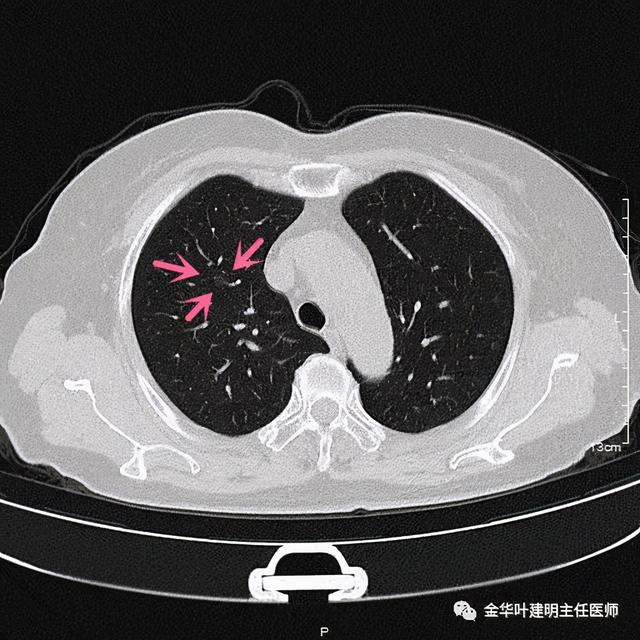

在右上叶前段(估计与尖段相邻近)有一直径约8毫米的淡磨玻璃结节 , 中间有一小点状偏高密度 , 从影像上看 , 考虑不典型增生或原位腺癌可能性大 。 再反过头再去找平扫的图像 , 真的不容易发现呀:

文章插图

这么淡的磨玻璃!